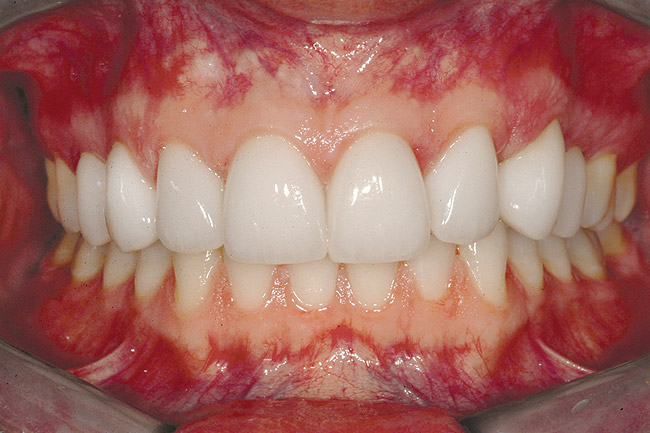

Fig 6 (and Fig 7). Prerestorative orthodontics was completed in 5 months. Final result 3 years, 4 months after completion.

Figure 6

Fig 7 (and Fig 6). Prerestorative orthodontics was completed in 5 months. Final result 3 years, 4 months after completion.

Figure 7

Fig 8 (and Fig 9). Teeth Nos. 5 and 12 were converted to Nos. 6 and 11, and Nos. 6 and 11 were converted to Nos. 7 and 10. Nos. 4 and 13 were enlarged. Note stability and absence of orthodontic relapse. Before-and-after smiles. Periodontist: Edward P. Allen, DDS, PhD. Prosthodontist: Robert R. Winter, DDS.

Fig 9 (and Fig 8). Teeth Nos. 5 and 12 were converted to Nos. 6 and 11, and Nos. 6 and 11 were converted to Nos. 7 and 10. Nos. 4 and 13 were enlarged. Note stability and absence of orthodontic relapse. Before-and-after smiles. Periodontist: Edward P. Allen, DDS, PhD. Prosthodontist: Robert R. Winter, DDS.